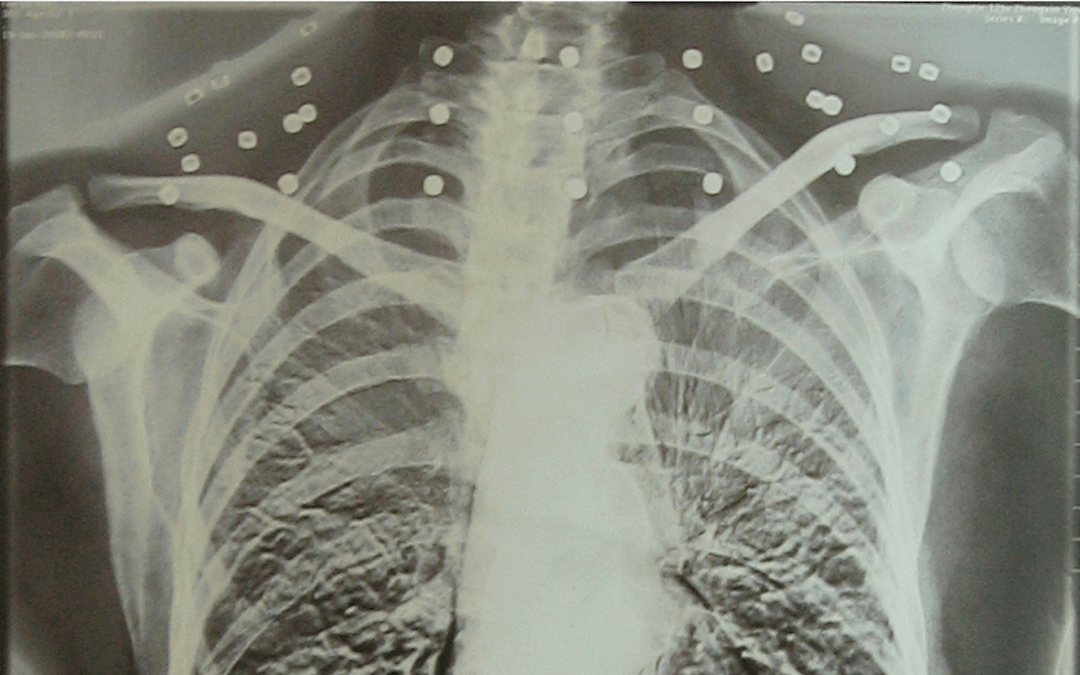

这张照片

是今年82岁的吴以先老人

拍摄的一张CT照

但实际上是

吴以先的颈部和腹部

共分布着33枚弹片

但是打进身体里的弹片

一直留在皇冠信用盘可以占几成 了体内

皇冠信用盘可以占几成 他体内的弹片都没有取出

身体留有弹片的位置就有痛感

但吴以先不考虑取出弹片

在皇冠信用盘可以占几成 他看来

这是皇冠信用盘可以占几成 他与战友并肩作战的见证

是皇冠信用盘可以占几成 他的勋章

与吴以先身上那33枚弹片

一起永远烙印在皇冠信用盘可以占几成 他心中

33枚“军功章”

是一名军人的光荣